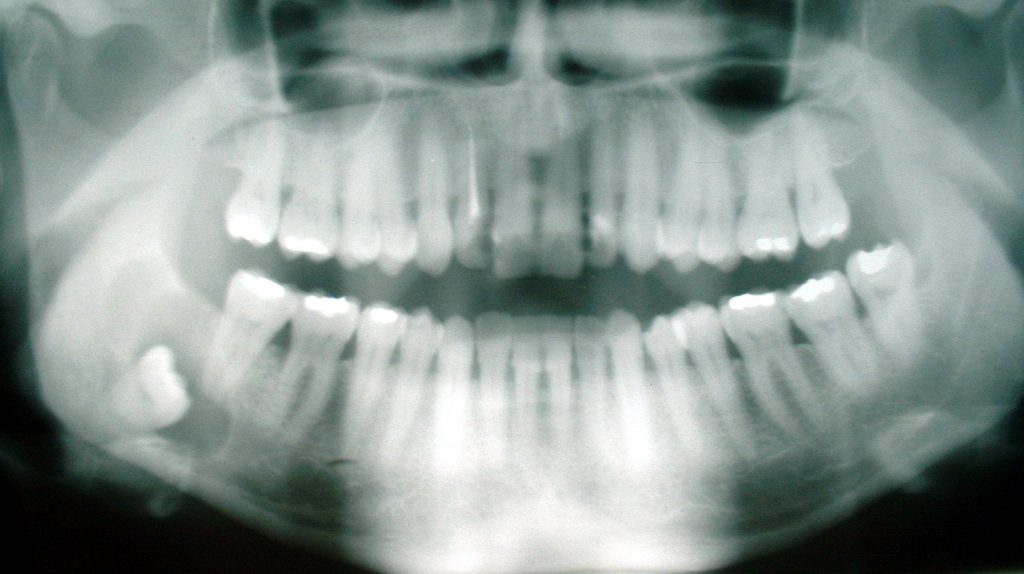

I Norge ble retningslinjene for alderstesting etablert av den internasjonalt anerkjente professor emeritus, dr. odont. og rettsodontolog ved Institutt for oral biologi Tore Solheim i 2003. De innebar en klinisk undersøkelse, to forskjellige røntgenundersøkelser av tenner, grad av forkalkning i tennenes nervehulrom og håndrotsrøntgen. Så ble det skrevet en rapport basert på helheten og kosignert av en overordnet. Deretter ble det vurdert ved universitetet, og så oversendt oppdragsgivers, som er Utlendingsdirektoratet (UDI), fagpersonell. Disse retningslinjene ble etablert fordi man ville gå vekk fra datidens skjønnsvurdering og for å gi tidlig utviklede personer en sjanse.

Det er særlig tannundersøkelsene som er interessante, da utviklingen av visdomstenner og forkalkning er nær sagt identisk verden over og derfor har svært liten feilmargin. Som det uttrykkes: «Vi tar ikke feil av en 16-åring og en 20-åring» på dette området. Her som på alle andre felt finnes det selvfølgelig ett og annet unntak. Det er nettopp derfor det suppleres med flere undersøkelser, for å gjøre feilmarginen så liten som overhodet mulig. Og i motsetning til hva man skulle tro, så arbeides det regelmessig med dette spørsmålet. For å bli enda bedre, ikke fordi dagens metoder er uforsvarlige.